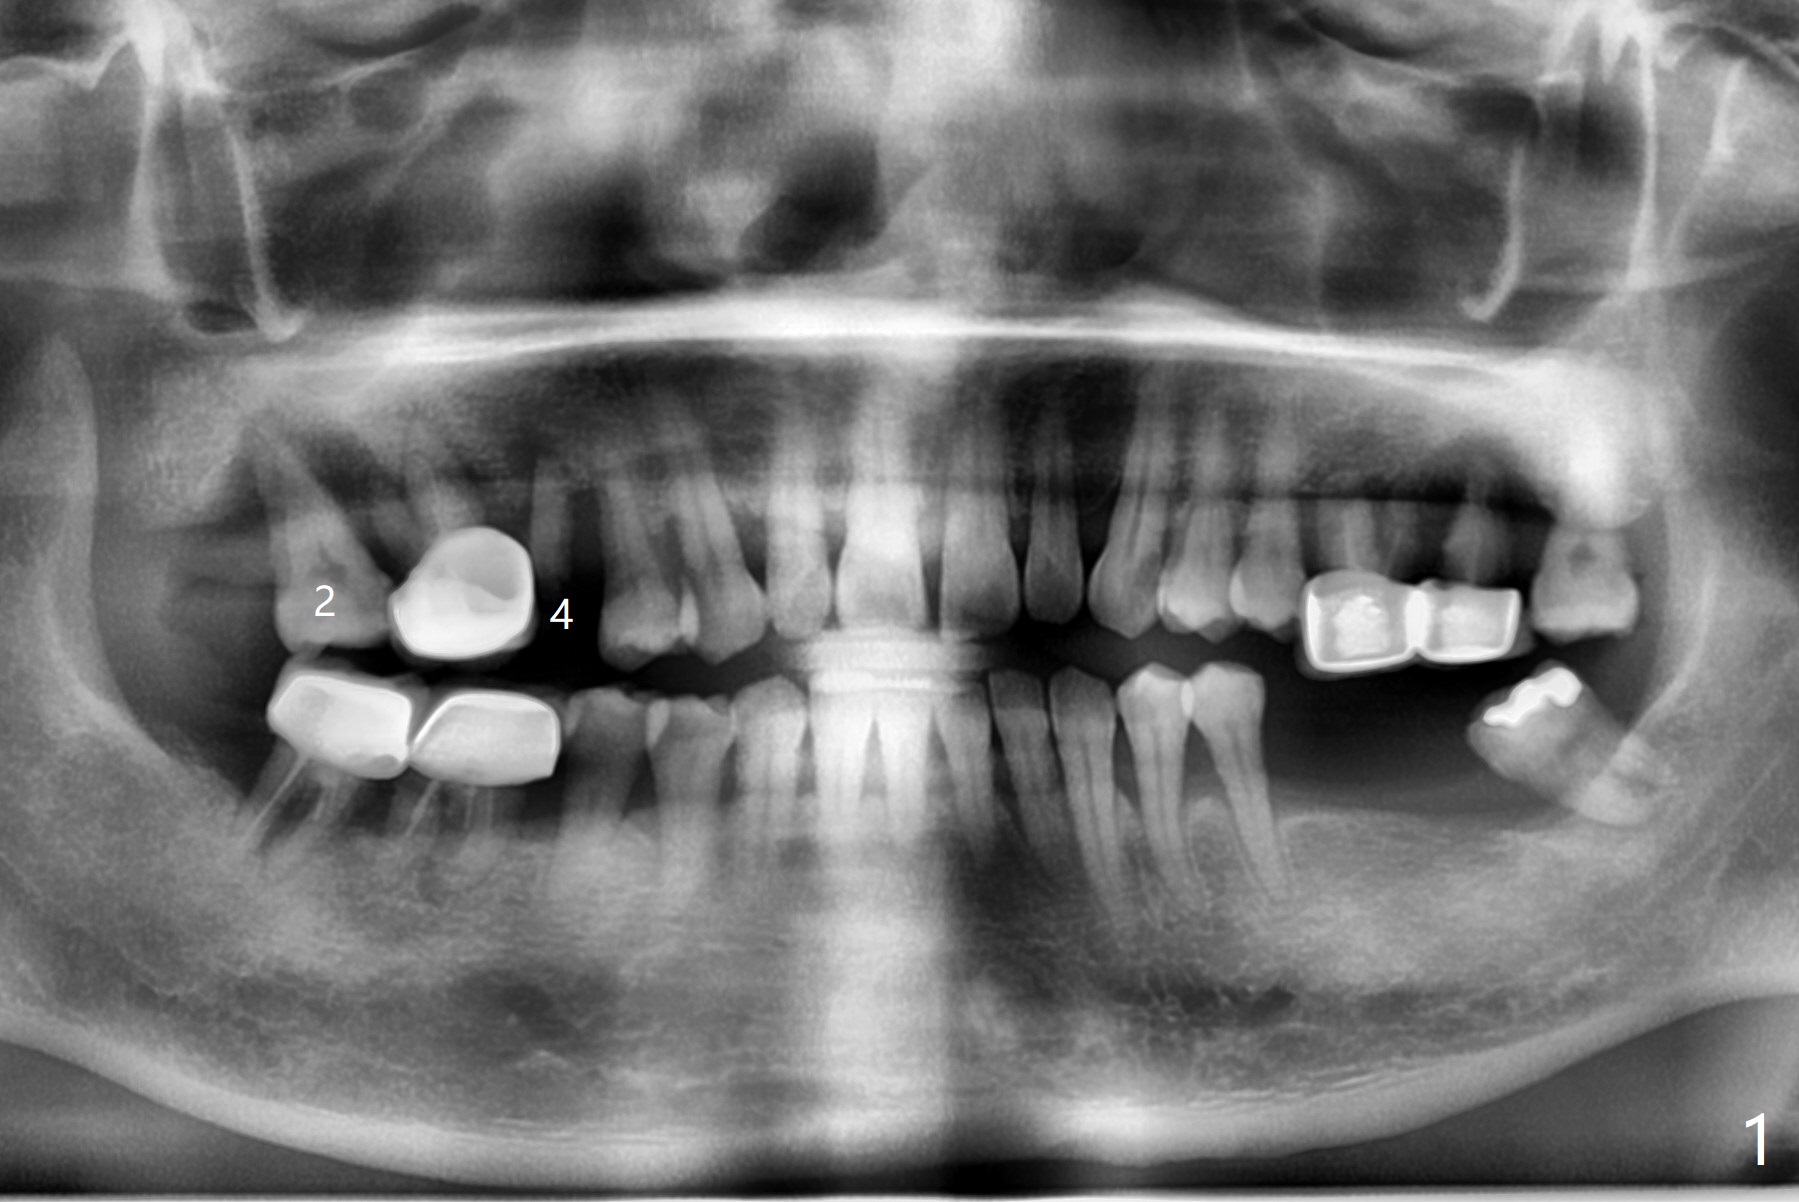

Away From Lesion

A 46-year-old woman wants to extract the mobile #2 and residual root of #4 for implants. She wants to save the tooth #3 with mobility II (Fig.1). Place an implant at #2 away from #3 (Fig.2). A small implant will be placed at #4 for the best possible trajectory (Fig.3). PRFx2.